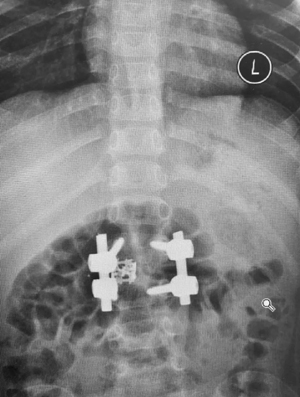

而对于何达主任医师带领的医疗团队来讲,面临着相同的挑战。孩子的年龄较小,增加了这次手术的难度,所有手术相关用物全部需要按照四岁孩子的标准进行匹配。术中,何达主任医师与韩晓光主治医师心理压力倍增,小心翼翼、准确无误的进行着每一步,最终两位医师配合默契,成功完成了手术。

手术中